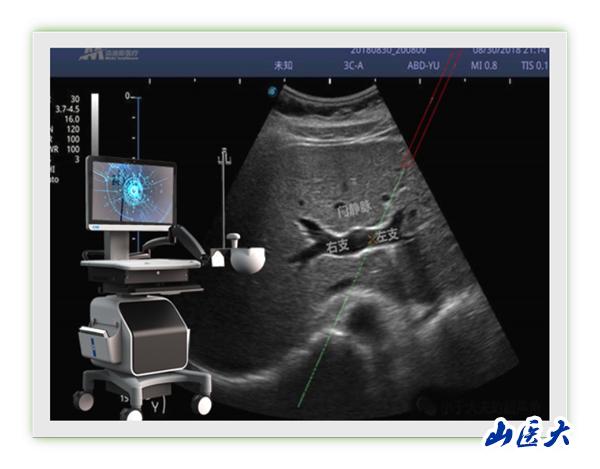

近日,第一醫院腫瘤與血管介入科馮對平主任團隊成功完成山西省首例超聲用電磁定位穿刺引導TIPS術。該技術將超聲圖像與電磁信號相融合,突破傳統超聲引導必須在平面內或平面外穿刺制約,能夠在任意位置、任意角度、任意平面穿刺靶點,真正實現實時三維穿刺導航。更為重要的是,該技術具有我國自主知識產權。馮對平說:“該新型穿刺引導技術能夠大大降低TIPS術中門靜脈穿刺難度,提高TIPS手術成功率,同時術者及患者受X線輻射時間也明顯縮短,值得進一步推廣應用。”